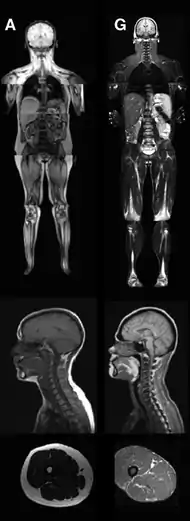

| An MRI image illustrating the lack of subcutaneous fat of a patient with the disease (G) compared to a control patient (A) | |